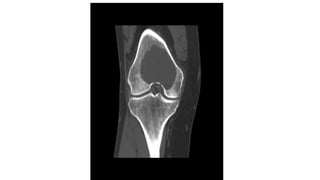

It occurs most commonly around the knee and at the

wrist after the epiphyses have fused. It isan expanding

destructive lesion, which is subarticular in position

Giant cell tumour

Giant cell tumour Hasfeatures of both malignant and benign tumours. It is locally invasive but rarely metastasizes. It occurs most commonly around the knee and at the wrist after the epiphyses have fused. It isan expanding destructive lesion, which is subarticular in position